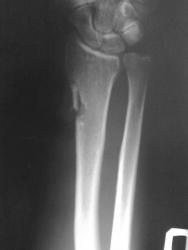

В связи с появлением и широкой популярностью шлифмашинок (в просторечии болгарки), травмы нанесенные этими прогрессивными агрегатами стали широко распространены. Характерной их особенностью являются переломы в виде линейных дефектов или ампутаций, чаще кистей-предплечий, стоп-голеней. Вот характерное наблюдение.

Еще предплечье, еще болгарка

ИзображениеИзображение